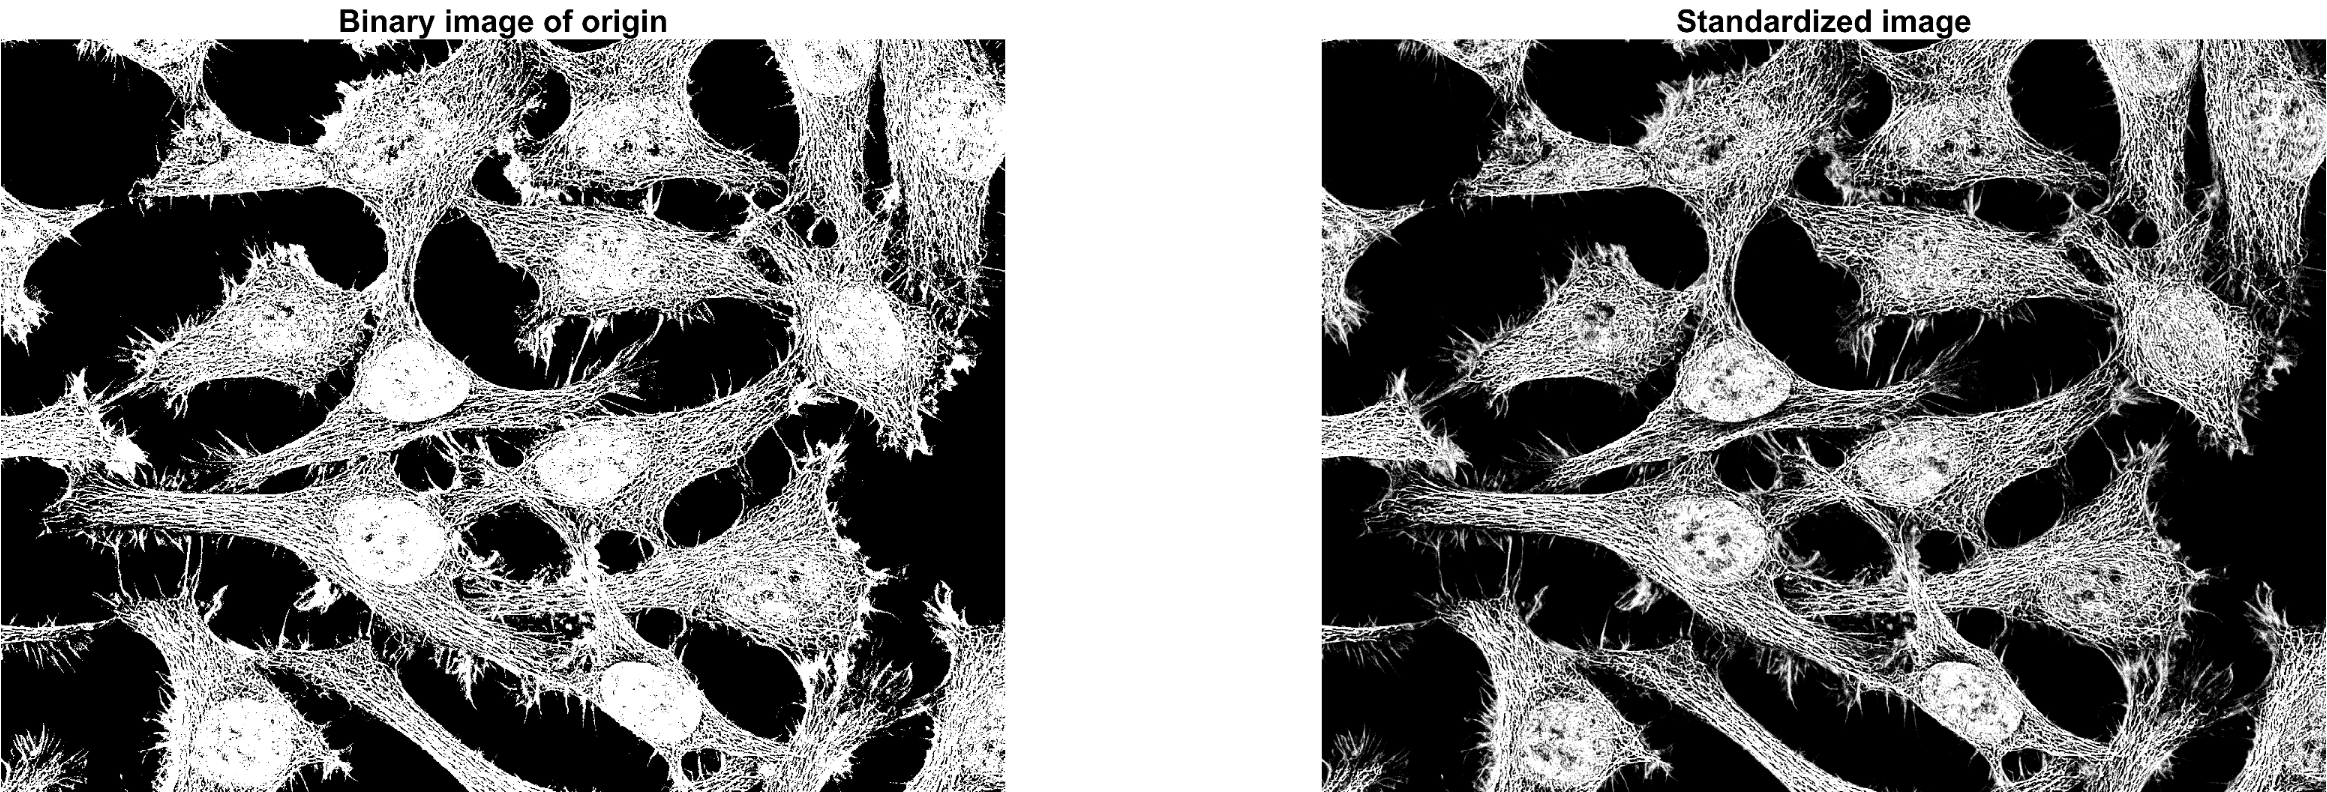

Standardization

앞의 normalization과 병행되는 또다른 이미지 품질 개선 테크닉을 소개합니다.

대상 이미지의 픽셀값 분포가 넓은 영역에 고르지 않고 어둡거나 밝은 영역에 편향적으로 분포되어

있다면 - 예를들어 histogram에서 어두운 영역에 급격한 높은 봉우리를 갖고 밝은영역에 긴 꼬리를

갖을경우 - standardization이 큰 도움이 될것입니다.

이것은 픽셀값의 분포를 평균(mean) 0, 표준편차(standard deviation) 1 을 갖도록 scale시켜 줍니다.

즉, 픽셀값 분포의 대부분은 "0" 을 중심으로 위치함으로써 분포를 평탄하게 해줍니다.

Standardization은 픽셀값에서 픽셀의 평균값을 뺀후 픽셀의 표준편차로 나누어 구합니다.

standardization = (X - Xmean) / Xstd, 여기서 X: 픽셀값, Xmean: 픽셀의 평균, Xstd: 픽셀의 표준편차

위의 결과 이미지 중 우측 이미지는 standardization을 수행한 결과로써 좌측의 Otsu 알고리즘을

이용한 Binarization 결과와 유사하게 보입니다. 그러나 우측의 standardization 결과 이미지를

자세히 본다면 cell(세포) 내, 외부의 미세한 형태적 특징을 좌측의 binarization 결과 보다 조금

더 자세히 볼 수 있습니다.

대상 이미지에 여러 cell(세포)들이 혼재한 경우 특정 cell(세포)을 추출 혹은 필터 마스크를

수행할 시, 개인적으로 미세한 형태적 특징을 고려해 binarization 보다는 standardization을

선호 합니다.